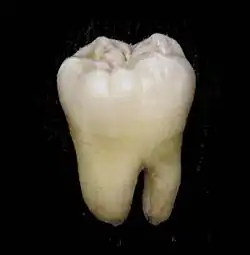

Jeder (echte) Zahn besteht aus der Zahnkrone (Corona dentis), dem Zahnhals (Cervix dentis, seltener: Collum dentis) und der Zahnwurzel (Radix dentis) und ist aus mehreren Schichten aufgebaut. Bei einem gesunden Zahn sieht man nur den Zahnschmelz, der wie eine Glasur das innen liegende Zahnbein (Dentin) bedeckt. Das Dentin wiederum umschließt das Zahnmark (Pulpa). Die Wurzel wird bis zum Zahnhals von Wurzelzement (Cementum) und Wurzelhaut umschlossen.

Zahnbein (Dentin)

Unter dem Zahnschmelz liegt das Zahnbein. Es stellt die Hauptmasse des Zahnes dar. Die Hartsubstanz des Dentins besteht wie beim Zahnschmelz aus Calcium und Phosphat, allerdings nur zu zwei Dritteln, der Rest ist Eiweiß und Wasser, weshalb Dentin weicher und anfälliger gegen Karies ist als der Zahnschmelz. Das Dentin ist schmerzempfindlich. Hitze-, Kälte- und Berührungsreize führen zu Flüssigkeitsbewegungen in den Dentinkanälchen (die im Bereich des Zahnhalses bis an die Oberfläche reichen können). Dies reizt die Tomes'schen Fasern, Zellfortsätze der Odontoblasten (dentinbildende Zellen). Die Odontoblasten stehen mit freien Nervenendigungen in Verbindung, die den Reiz als Schmerzempfindung ans Zentralnervensystem weiterleiten.

Das Dentin ist wesentlich elastischer als der Zahnschmelz (Elastizitätsmodul 15.000–20.000 MPa), da es über einen deutlich höheren Anteil an organischer Substanz verfügt. Die Vickershärte beträgt beim Zahnbein 60–70 und die Druckfestigkeit liegt bei 200–350 MPa (Körber, 1995).[7]